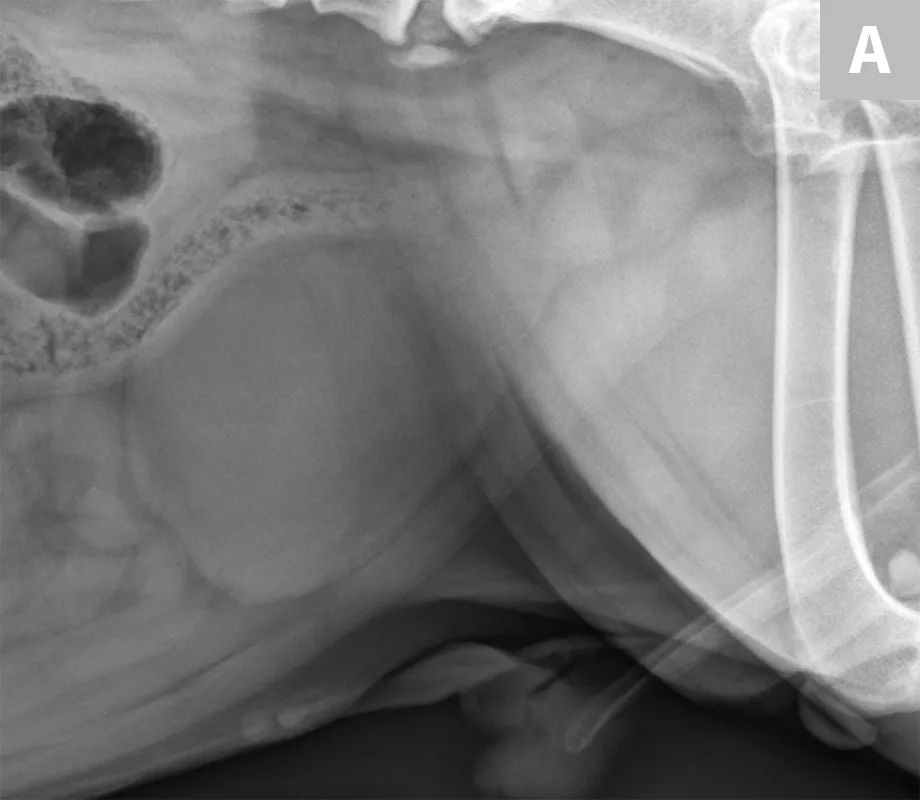

FIGURE 7A

Lateral abdominal radiograph of a cat with multiple, small, oval mineral opacities superimposed over the ventral aspect of the retroperitoneal space (arrows). These mineral opacities are arranged linearly extending from the caudal aspect of the kidneys to the level of the urinary bladder.